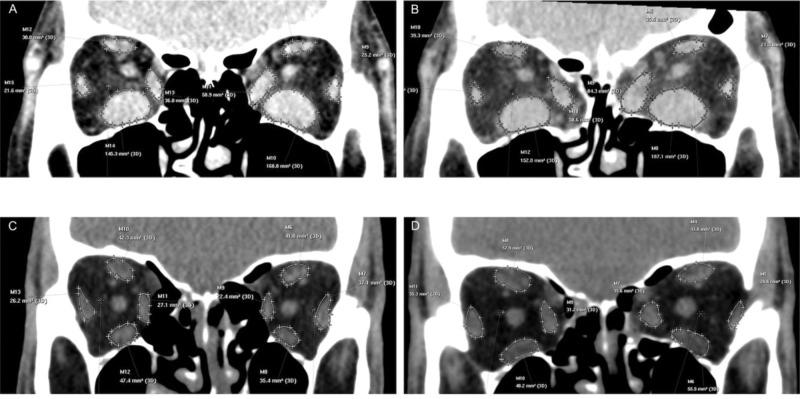

Forty-two patients with inactive GO eligible for OD were randomly assigned to either the IM-OD or ML-OD groups. Pre and postoperative evaluations included Hertel exophthalmometry, sensory, and motor extraocular motility assessment, standardized photographs in the nine gaze positions, and computed tomography (CT) of the orbits. ClinicalTrials.gov: NCT03278964.

Exophthalmometry reduction was statistically significant in both groups (p<0.001), but was greater in the ML-OD group (p=0.010). New-onset esotropia occurred in 11.1% and 23.5% of patients who underwent IM-OD and ML-OD, respectively, with no statistically significant difference in the frequency of pre and postoperative strabismus in either group. The mean increase in preoperative esotropia was 24±6.9 and 12±8.8 prism diopters in patients who underwent IM-OD and ML-OD, respectively. In the IM-OD group, abduction and elevation worsened at the first (p<0.05) and third (p<0.05) postoperative visits but were restored at 6 months. The versions did not change postoperatively with ML-OD. The preoperative CT-measured medial rectus muscle area predicted new-onset strabismus (p=0.023). Significant postoperative medial rectus muscle enlargement occurred in both groups (p<0.001). Restriction in elevation and abduction was significantly associated with enlarged inferior (p=0.007) and medial rectus muscle areas (p=0.002).

两组患者的眼球突出度降低均具有统计学意义(p<0.001),但ML-OD组降低幅度更大(p=0.010)。接受IM-OD和ML-OD的患者分别有11.1%和23.5%发生了新发内斜视,两组术前和术后斜视发生率无统计学差异。接受IM-OD和ML-OD的患者术前内斜视平均增加量分别为24±6.9和12±8.8棱镜度。在IM-OD组,术后第一次(p<0.05)和第三次(p<0.05)随访时外展和上抬功能恶化,但在6个月时恢复。ML-OD术后各方向运动功能未发生改变。术前CT测量的内直肌面积可预测新发斜视(p=0.023)。两组术后内直肌均有明显增大(p<0.001)。上抬和外展受限与下直肌(p=0.007)和内直肌面积增大(p=0.002)显著相关。